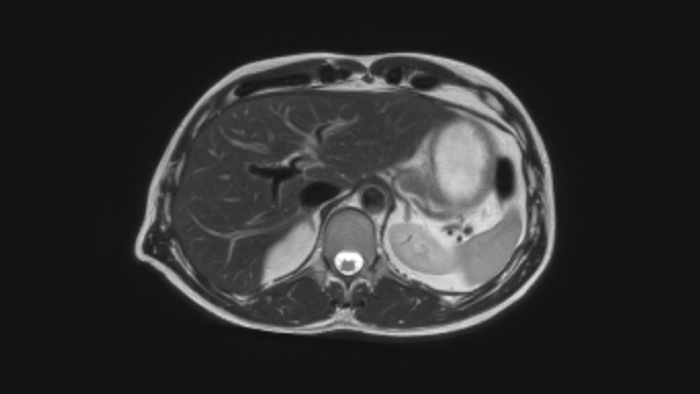

Діагностична точність Розширте свої можливості візуалізації в усіх клінічних областях. Дізнайтеся, які переваги отримують ваші колеги.

Тепер ви можете отримати все це із системою Ingenia Ambition. Вона надає можливості для покращення МРТ на всіх рівнях.

Швидкість і& комфорт Зниження необхідності затримки дихання на 40% без втрати якості зображення4.